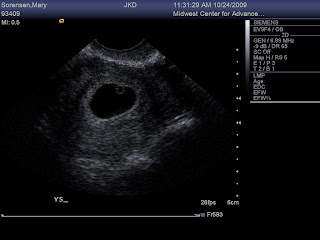

We got to see our little bean and we saw the heartbeat! The due date was confirmed and is still June 11th!! We are thinking of doing a pool for the due date and weight of the baby for some fun!